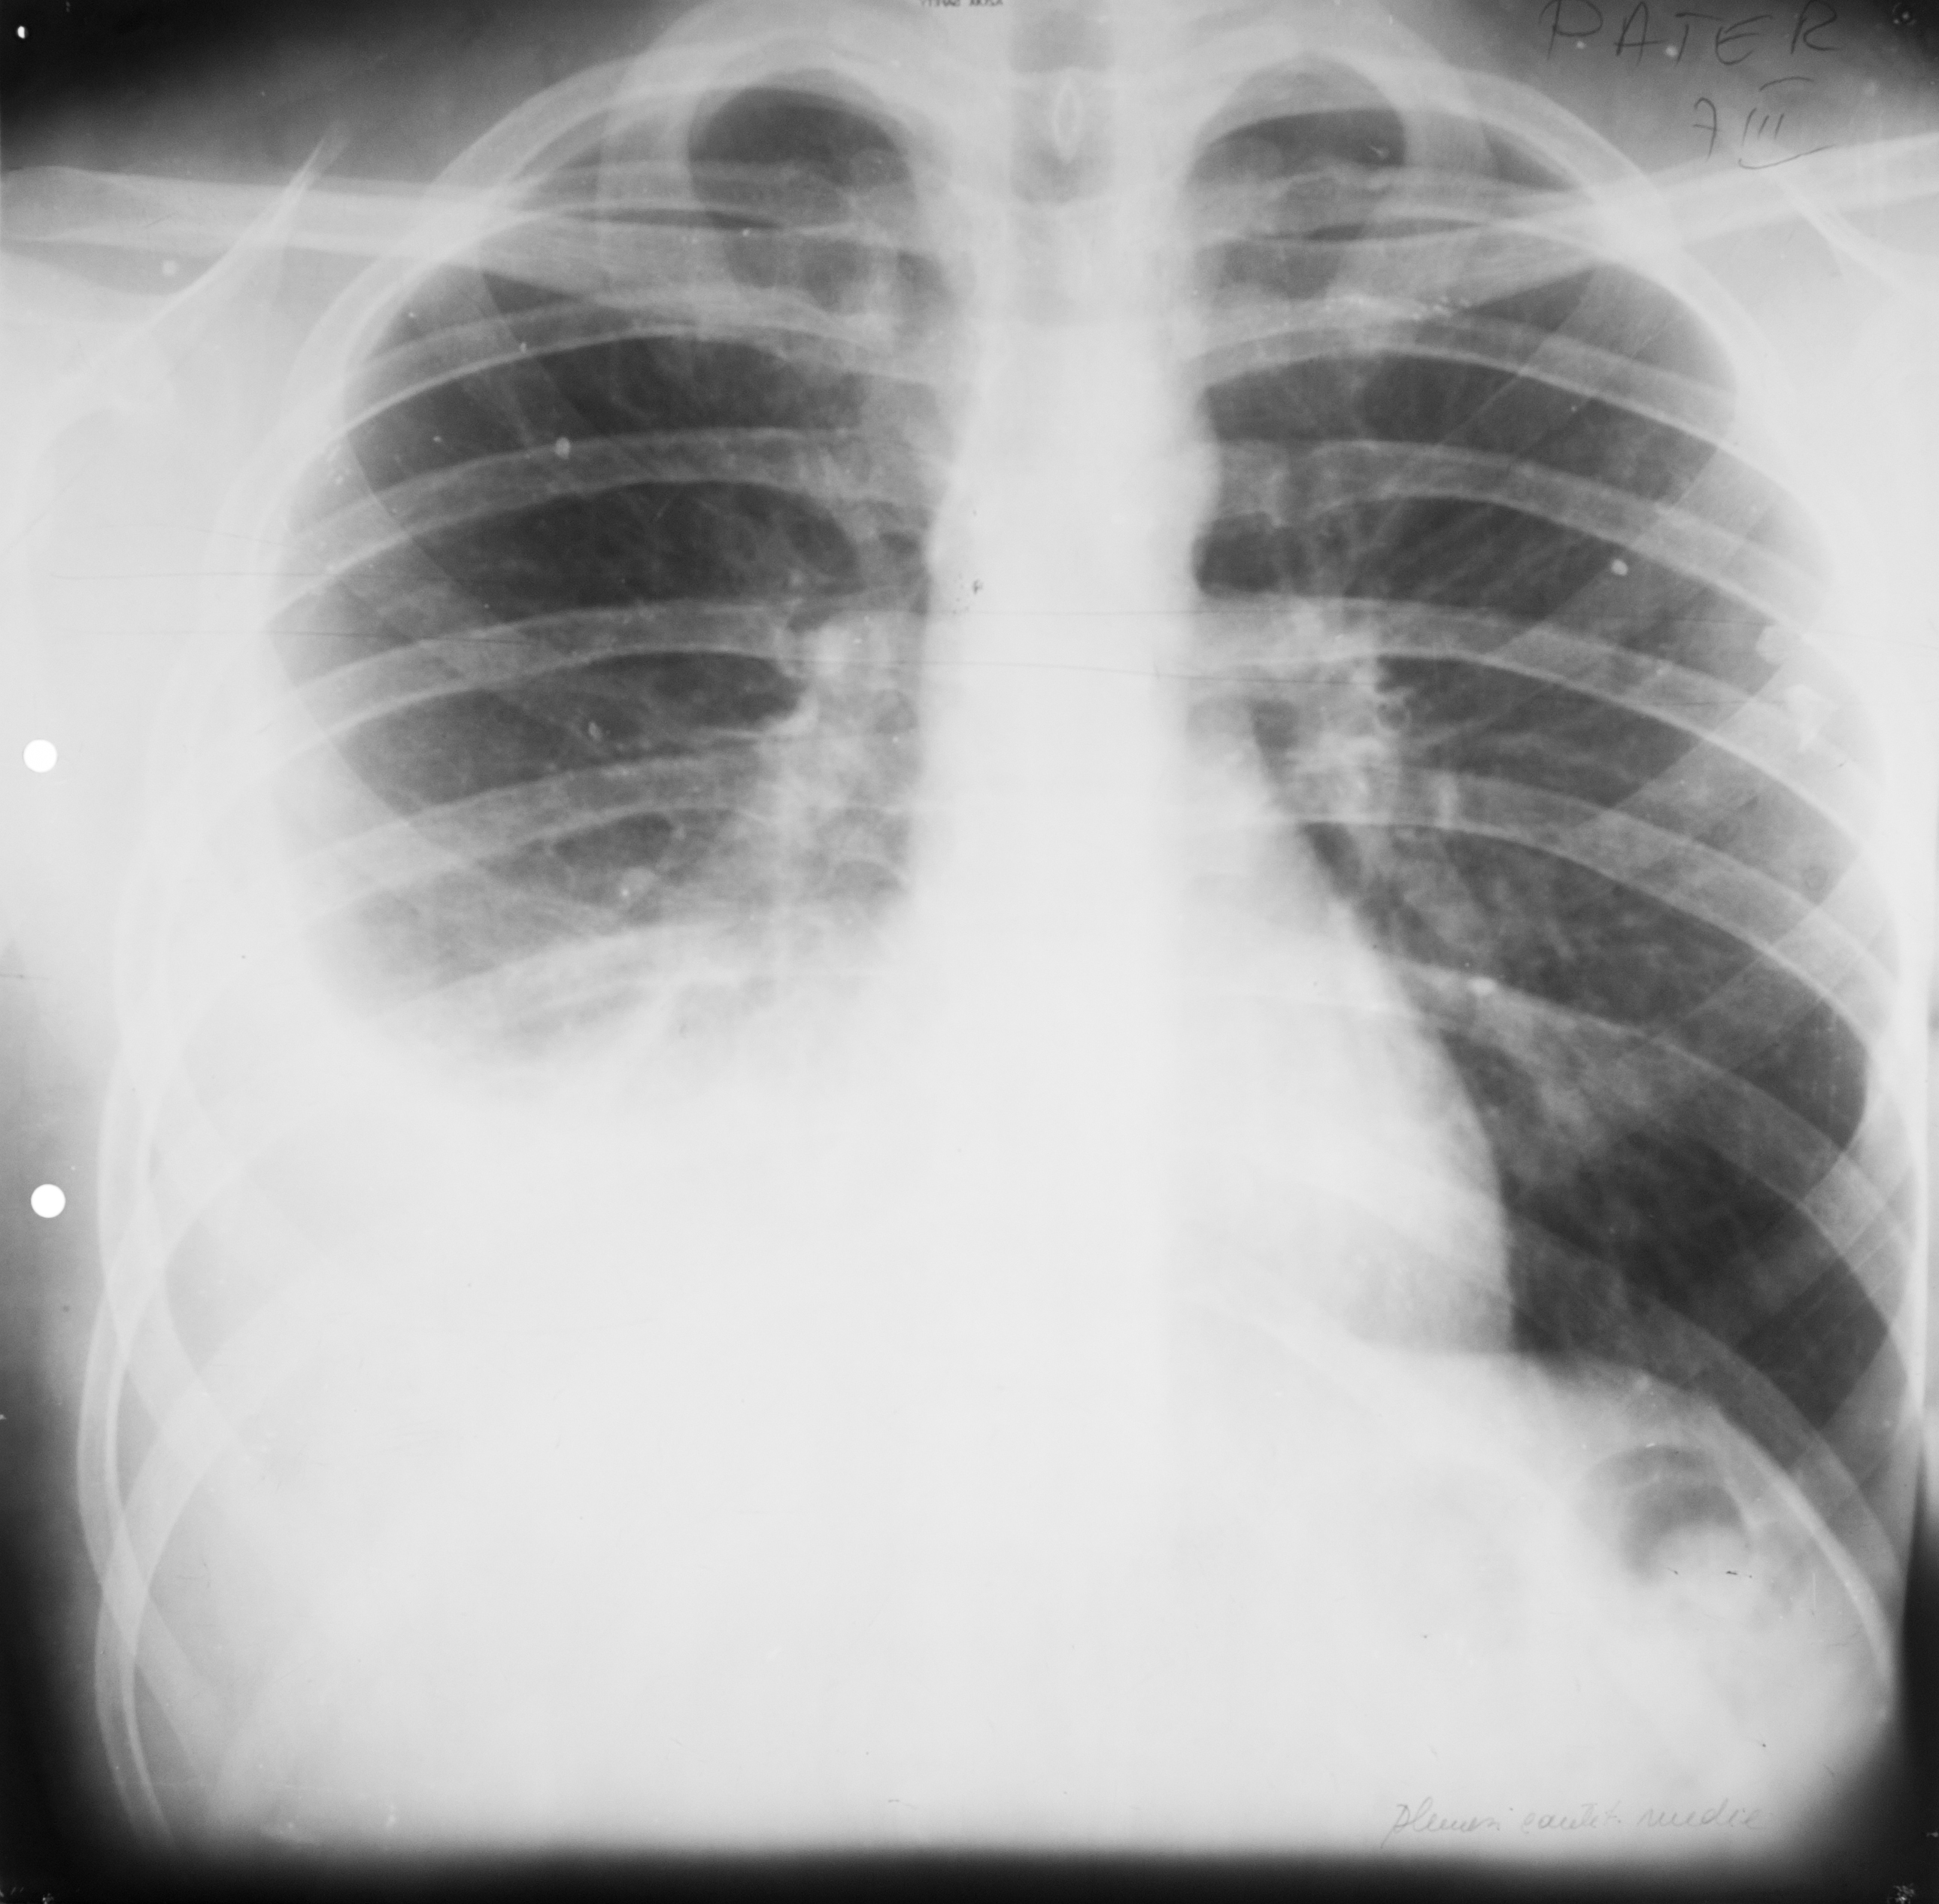

Rx toraco-mediastino-pleuro-pulmonară – opacitate la bazele plămânilor,de intensitate medie,situată la nivelul sinusurilor costo-diafragmatice,care nu mai sunt ascuțite,ci sunt închise/întinse ?,colecție pleurală

COLECȚIE PLEURALĂ

Opacitate întinsă situată bazal dreapta,intensitate medie,omogenă cu concavitate orientată cranial

Aceleasi opacitati la baza campurilor pulmonare cu concavitatea orientata cranial,dar de dimensiuni mai mici – colectie pleurala bilaterala

Opacifierea unui intreg camp pulmonar cu impingerea cordului si a mediastinului spre partea sanatoasa – colectie pleurala masiva